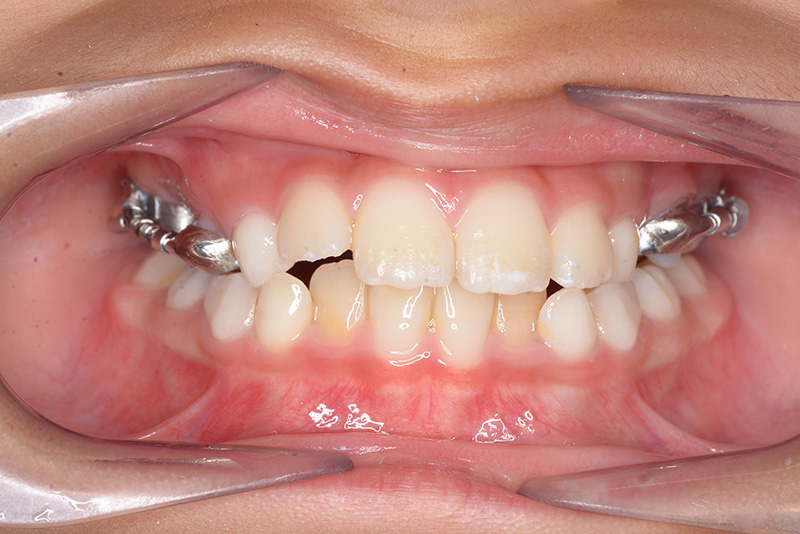

| 口腔内所見 | over jet 2.5mm、over bite 2.0mm、右側大臼歯関係はEnd on class Ⅱ、上顎左側Eは早期喪失により左側大臼歯関係はFull classⅡ、右側Eは6の異所萌出により歯根吸収が進行したため一般歯科医院にて抜去済みであった。 |

| パノラマ所見 | 上顎両側6、特に左側6は近心傾斜が認められ、両側5の萌出スペース不足が認められた。 |